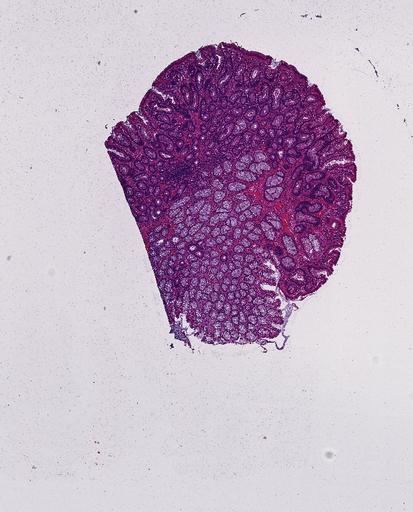

High‑resolution three‑dimensional (3D) tissue atlases promise to redefine how we study cellular architecture‑function relationships in human tissues. Large-scale consortia such as the Human Bimolecular Atlas Program (HuBMAP) systematically build detailed 3D organ maps by profiling serial tissue sections with single-cell spatial technologies. However, an accurate and efficient reconstruction method that can handle atlas-scale datasets remains elusive. We introduce Space-map, an open-source method that integrates single‑cell coordinates with optional histological image features to assemble serial sections into 3D models. Space‑map combines multi‑scale feature matching with large‑deformation diffeomorphic metric mapping, delivering global reconstructions while preserving local micro‑anatomy. To demonstrate the capability of Space-map, we generated a serially sectioned spatial transcriptomics (Xenium, ~2.9M cells) dataset and a spatial proteomics dataset (CODEX, ~2.4M cells). Applying Space-map to these single-cell spatial maps, we built three 3D models for both diseased (colon polyp) and reference colon tissues. These high-resolution 3D models showcase the intricate structure of the human colon across different states. Space-map is fast and highly efficient. We demonstrated its performance and accuracy using in‑house and public datasets. The result shows that Space‑map is 10 times faster and ~2‑fold more accurate than PASTE and STalign, making 3D atlas reconstruction more accessible. Our study provides a new robust and user-friendly software available at https://github.com/a12910/spacemap that can be easily applied for constructing molecular 3D tissue maps of human organs at single-cell resolution.